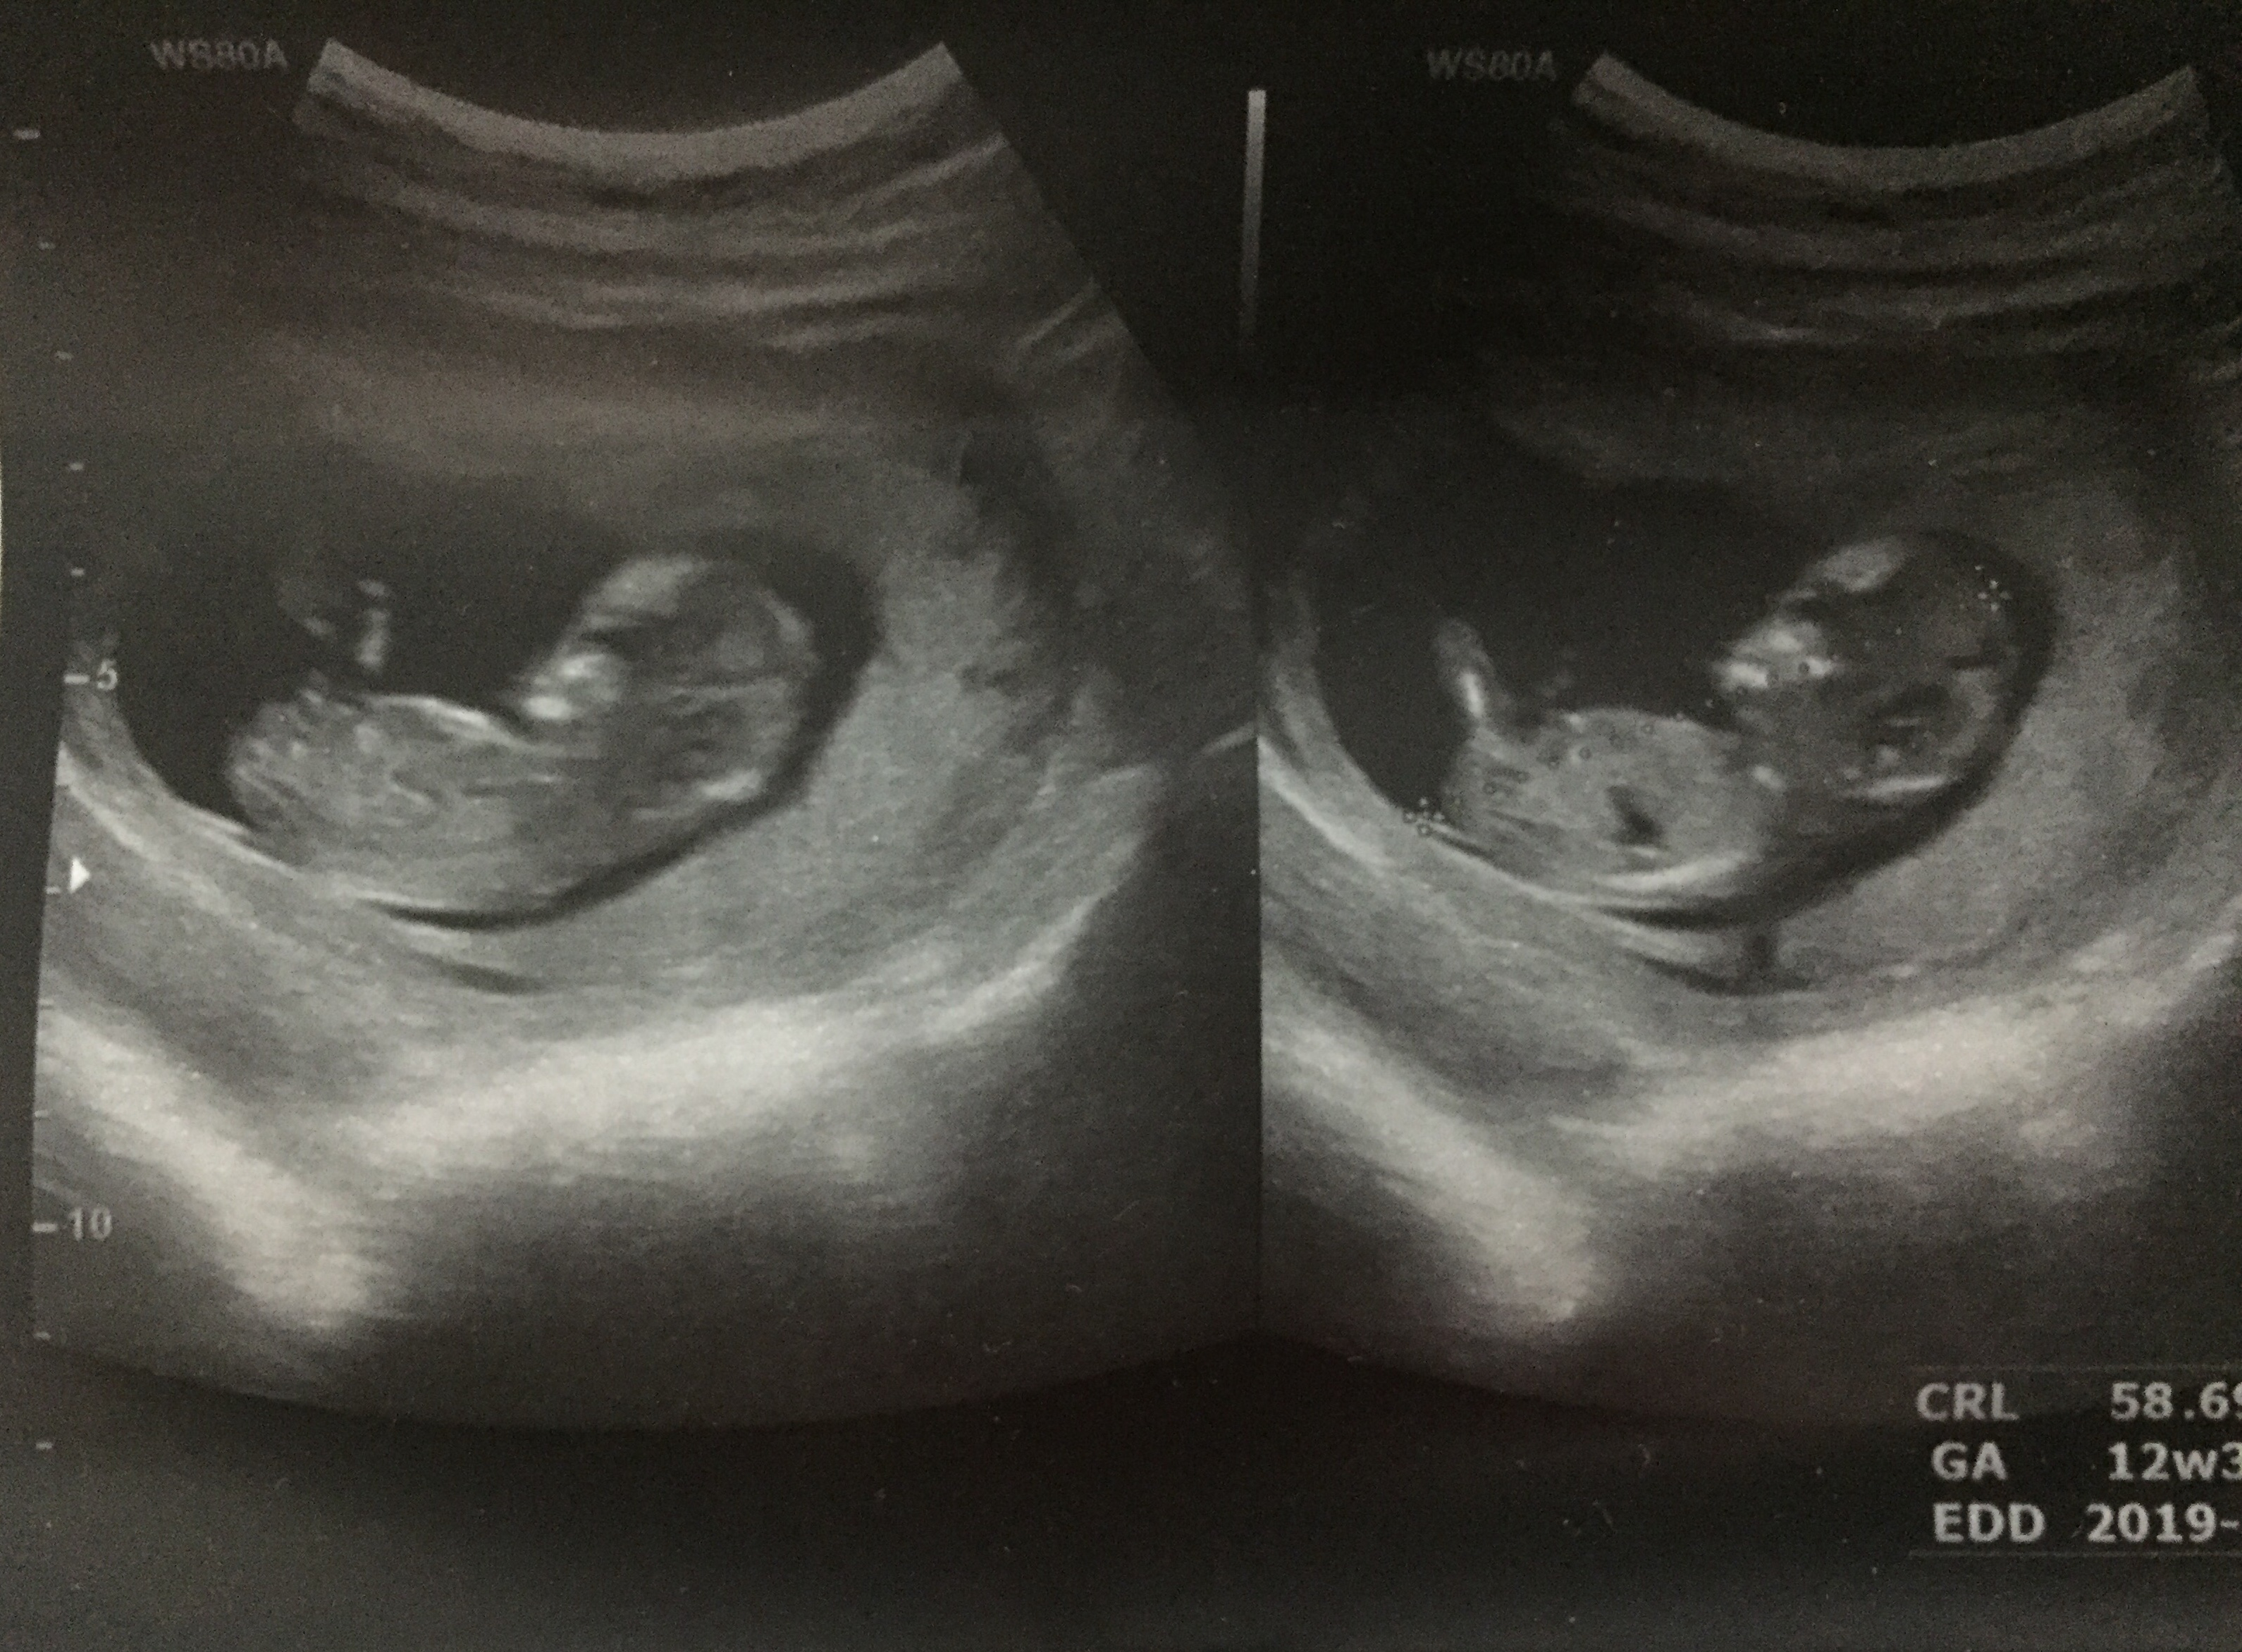

lili95 مدیر استارتر عضویت: 1397/05/06 تعداد پست: 832 عنوان تعيين جنسيت 144 بازدید | 13 پست بچه ها عكس سونوي nt مو ميذارمبه نظرتون بيشتر شبيه دختراس يا پسرا؟؟؟ 1397/09/18 | 14:30 0 نفر لایک کرده اند ... گزارش تاپیک نامناسب

lili95 مدیر استارتر عضویت: 1397/05/06 تعداد پست: 832 خب احتمالاتش چی بود؟ چون معمولا درست در میاد گفت پسر

برباد_رفته عضویت: 1397/02/04 تعداد پست: 17064 گفت پسر دیدی گفتم سرش مثل پسراست😊ایشالا هرچی هست زنده و سلامت باشه. و سایه شما و شوهرتم بالای سرش